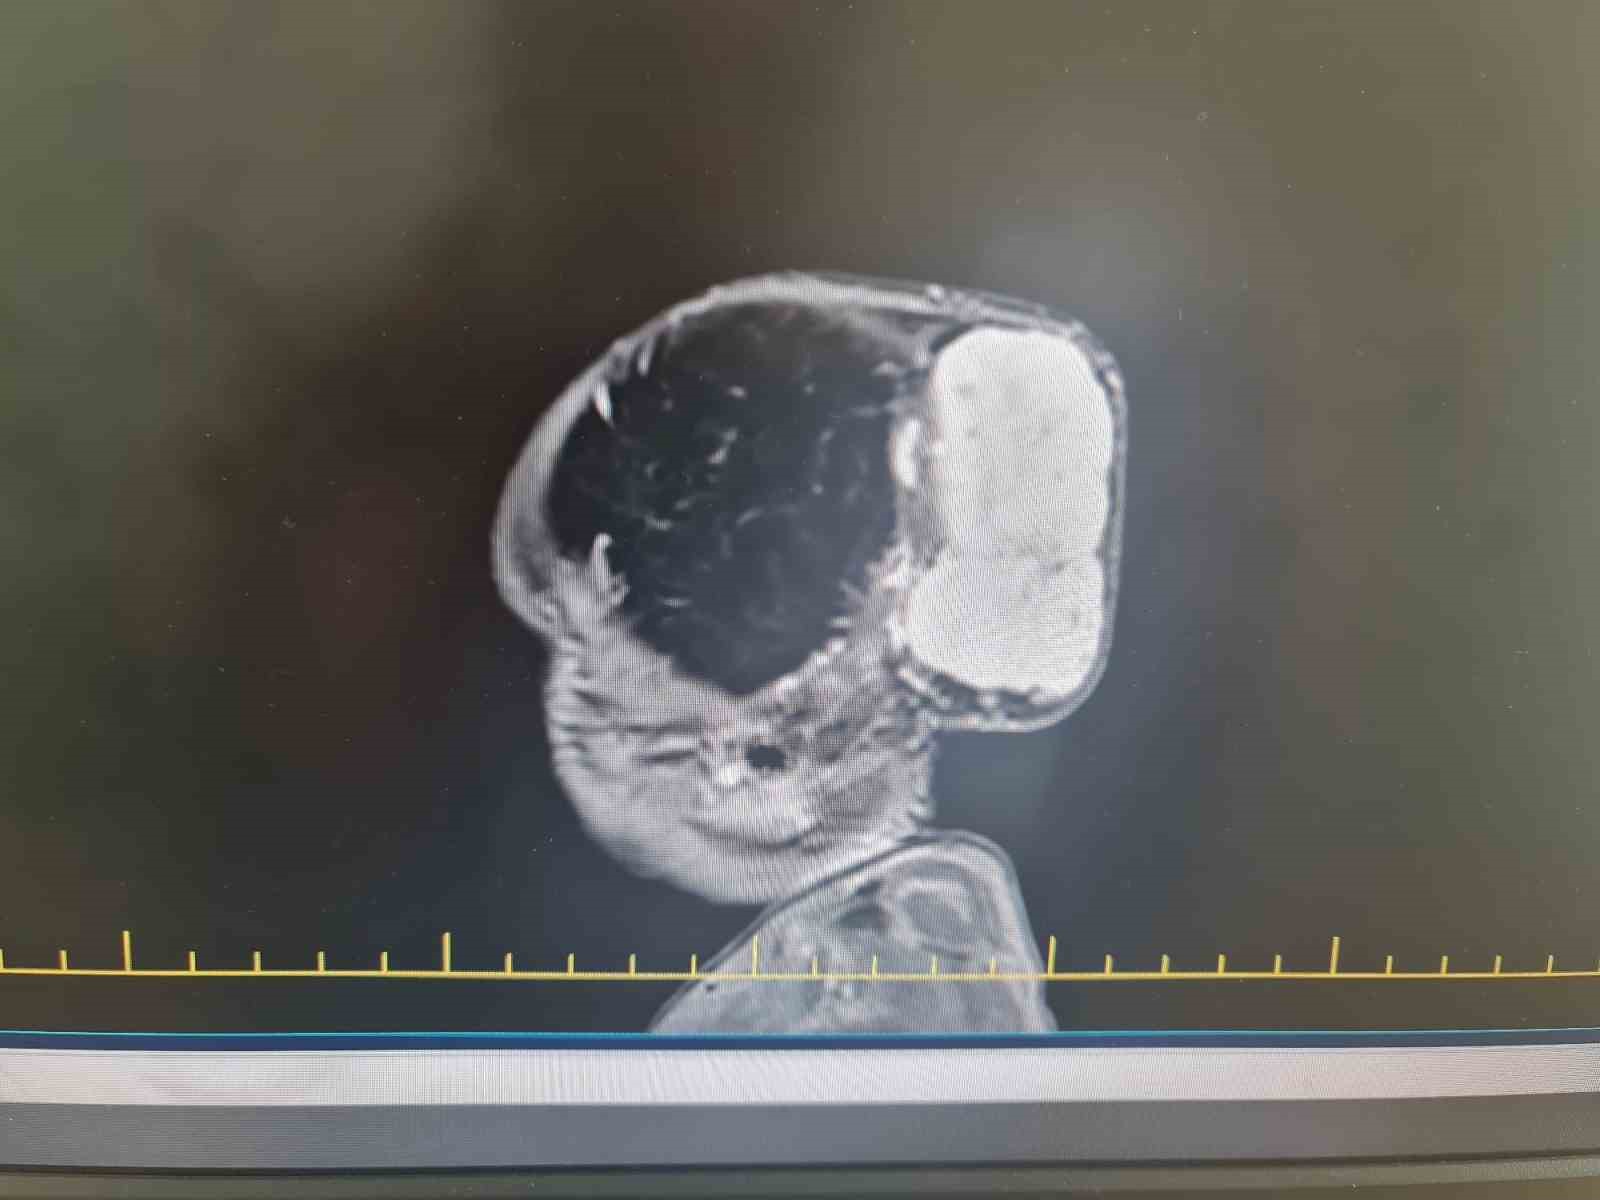

Gaziantep’te Yalçın Enes ve Tuğba Yalçın çiftinin 1,5 yaşındaki çocukları Talha, Gaziantep Şehir Hastanesinde kafasında büyük bir kitle ile dünyaya geldi. Aynı hastanede yapılan tetkiklerde minik Talha’nın kafatasında 7 x 6,5 x 4 santimetre boyutlarında, dünyada nadir görülen vakalar arasında yer alan bir tümör tespit edildi.

Op. Dr. Ali Yayla, "Hastamız Talha bebek, başında dev bir kitle ile doğdu. Yaptığımız tetkikler ve görüntüleme sırasında tümörün hızla büyüdüğünü ve kafa tası kemiklerini harap ettiğini, beyne de baskı yaptığını gördük. Bunun üzerine ameliyat planladık. Fakat bu tümörün özelliğinden dolayı çok fazla damar yapısı vardı. Kanlanması çok fazlaydı ve tümörün kanama riski nedeniyle hayati tehlikesi bu cerrahi işlemle yüksek düzeydeydi. Bu nedenle cerrahi stratejimizi tekrar ve yeniden kurduk. Buna göre basamaklandırılmış ve multidispliner bir yaklaşım sunduk. Öncesinde girişimsel radyoloji ekibi hastaya bir embolizasyon işlemi yaptı ve tümörün kanlanmasını azalttı. Hemen bir gün sonra plastik cerrahisi ve beyin cerrahisinden oluşan bir ekiple, yaklaşık 4 saat süren bir ameliyatla tümörün tamamını başarılı bir şekilde çıkardık. Hastamız bundan herhangi bir zarar görmedi ve sağlığı da gayet iyi seyrediyor. Çocuğumuzu ailesine sağ salim teslim ettik. Tabii bu işlemin arka planında çalışan yeni doğan çocuk yoğun bakım, çocuk hematolojisi, beyin cerrahisi, plastik cerrahi, anestezi olmak üzere büyük bir ekip var. Doktorundan hemşiresine ve sağlık personeline, bütün hastane yönetimine bir buçuk ay boyunca gayret gösterildi ve sonunda da çocuğumuz sağ salim bir şekilde ailesine teslim edildi" dedi.

Bu tarz tümörlerin nadir olarak görüldüğünü aktaran Op. Dr. Ali Yayla, bebeğin taburcu olmasında herhangi bir sorun olmadığını söyleyerek, "Tümörün boyutları yaklaşık 7 x 6,5 x 4 santimetre çaplarındaydı. Bu büyüklükte bir tümör dünyada nadir bir şekilde bu yaş grubunda görülebiliyor. Bu operasyonu başarılı bir şekilde Gaziantep Şehir Hastanesi’nde uygulamak da bizim için büyük bir gurur oldu. Taburcu olmasında herhangi bir sorun yok bugün dördüncü günü. Ama biraz daha bekleyip güvende olmasını istiyoruz. Dolayısıyla dördüncü gün tamamladık, beşinci gün taburcu olabilir" ifadelerini kullandı.